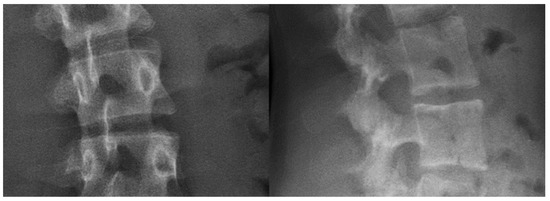

Three vertebrae (each 3D-printed with one of the above settings) were then imaged with EOSedge® (the latest EOS imaging device). Figure 3 shows that the customized filling “vertical grid 5°” setting obtains the most realistic radiographic rendering, with a uniform texture of cancellous bone and a significant signal in cortical bone. Bi-planar X-ray images of actual patient vertebrae and the surrounding soft tissues are presented in Figure 4 for comparison.

Figure 3. Bi-planar X-rays of three 3D-printed vertebrae, each resulting from different printer settings. From top to bottom: quarter cubic 45°, hole’s infill, and personalized vertical grid 5°.

Figure 4. Bi-planar X-rays of the spine of an actual patient.